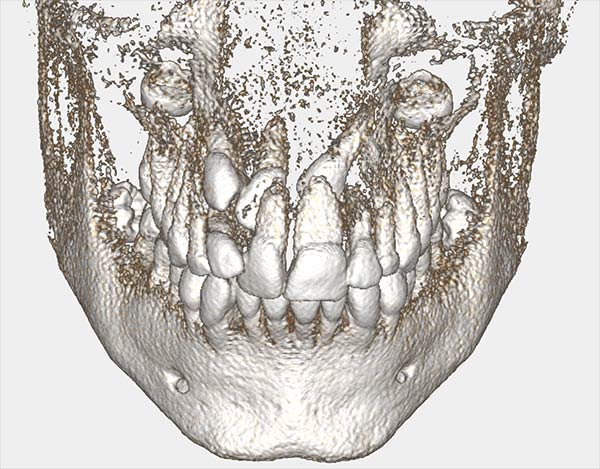

Αν κρίνεται απαραίτητο λαμβάνονται φωτογραφίες και ζητούνται ακτινογραφίες, συνηθέστερα πανοραμική αλλά και κεφαλομετρική, ενώ σε ειδικές περιπτώσεις μπορεί να χρησιμοποιηθούν και τομογραφίες. Τα παραπάνω μελετώνται με επιμέλεια προκειμένου να υπάρξει σαφέστερη κατανόηση κάθε προβλήματος και να βελτιστοποιηθεί το θεραπευτικό πλάνο.